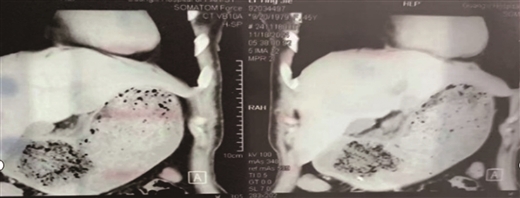

今年的4月15日—21日是第31个全国肿瘤防治宣传周,伴随着医疗技术的不断发展和普及,射波刀作为立体定向放射外科治疗方式,开始走入大众视野,它...

2025年全国肿瘤防治宣传周(4月15-21日)期间广西中医药大学附属瑞康医院(自治区中西医结合医院)倾情推出公益支持计划具有射波刀治疗指征且享...